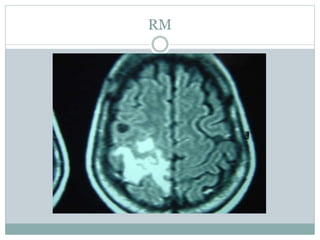

RM